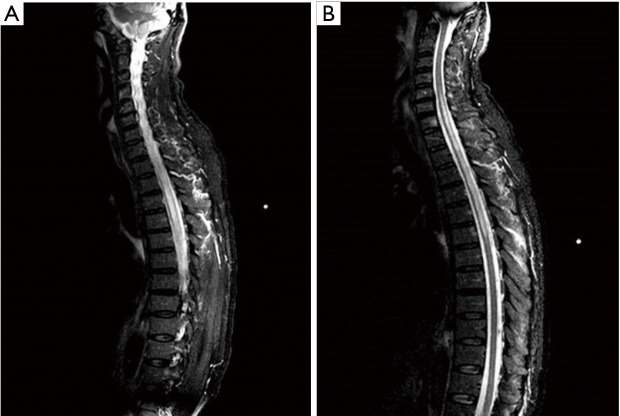

Case description: A 58-year-old Caucasian man was admitted to the Emergency Department (ED) with low back pain and walking inability. He had an unsteady gait, paraesthesia of the lower limbs and pain in the left lumbar area of the spine. He previously manifested repeated episodes of Raynaud's phenomenon. The neurological examination revealed pyramidal signs with asymmetric and progressive paraparesis associated with hypoesthesia and bladder dysfunction. A spine magnetic resonance imaging (MRI) revealed the presence of a long extensive cervico-dorsal myelitis. Among laboratory analyses, serum immunometric examinations came back positive for anti-RNP (272 U/mL) and anti-SSA (20 U/mL) antibodies, whereas a recombinant immunofluorescence assay revealed the presence of immunoglobulin G (IgG) antibodies against AQP4. Consequently, he was treated with high-doses of corticosteroids, with progressive resolution of symptoms. To date, his last cervico-dorsal spine MRI showed negative results.